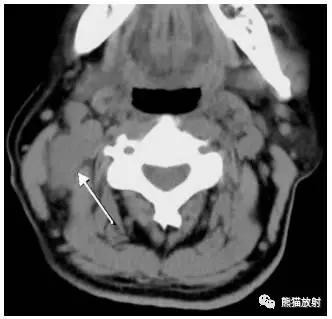

舌骨上水平CT增强图像

横白线在两侧颌下腺后缘。

线以前为I区淋巴结,线后为II区淋巴结。在颈内静脉附近为IIA区,颈内静脉后面不接近静脉的淋巴结为IIB区。